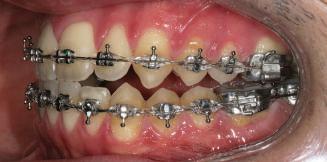

20 Dental Tribune Bulgarian Edition / октомври 2022 г. П ациентите със завършен растеж и скелетни проблеми обикновено представляват предизвикателство за ортодонт ската практика. Необходимостта от изваждане на зъби в комбинация с особеностите на възрастовата ортодонтия изисква особено внима ние. Фокусът върху критично важното значение на позицията на долните резци във връзка с дългосроч ната стабилност и постигането на оптимални оклузални взаимоотношения при затварянето на екстракционните пространства лесно може да излезе извън контрол. Когато към тези чисто кли нични проблеми се добави и стресът от натоваре ната практика, предизвикателството става още по-голямо. Всички тези фактори налагат използ ването на доказан подход с ясни и последовател ни стъпки, в което се разкрива силата на дисциплината „Алекзандър“ – предвидим протокол през целия процес на елиминиране на ротациите, ниве лиране на дъгите, затваряне на екстракционните пространства и финализиране на случая. Именно такъв е и случаят, който презентираме –екстракционен, скелетен клас 3 при възрастен па циент, лекуван по системата „Алекзандър“. ПРЕДВИДИМИ РЕЗУЛТАТИ ПРИ ПАЦИЕНТИ СЪС ЗАВЪРШЕН РАСТЕЖ И СКЕЛЕТЕН КЛАС 3, ИЗПОЛЗВАЙКИ ЕКСТРАКЦИОННО ЛЕЧЕНИЕ ПО ДИСЦИПЛИНАТА „АЛЕКЗАНДЪР“ Д-р Радой Димитров, България Преди започване на лечение клиничен случай | ортодонтия Фиг. 1а–1e Преди започване на лечение. Пациентът пристига в практиката с основното оплакване от невъзмож ност за нормално дъвчене. Снета е цялата необходима диагностична ин формация. Фиг. 1f–1h Снимки в профил и анфас. Фиг. 1i–1k Панорамна снимка, телерентгенография и анализ на телерент генография. Фиг. 1а Фиг. 1d Фиг. 1f Фиг. 1g Фиг. 1h Фиг. 1e Фиг. 1b Фиг. 1c Фиг. 1i Фиг. 1j Фиг. 1k

closed.

21Dental Tribune Bulgarian Edition / октомври 2022 г. ДИАГНОСТИЧНИ РЕЗУЛТАТИ: 1. Възраст на пациента: 21 години 2. Скелетен клас III (ANB 0) 3. Зъбен клас 3 4. Ръбцова захапка във фронта, кръстосана в дисталните участъци 5. Тясна горна челюст 6. Overjet – 0 мм, Overbite – 0 мм 7. Несъответствие на горната с долната средна линия 8. Единични контакти в ЦО 9. Хиподивергентен тип на растеж SN/MP – 33.5 10. Неравен гингивален контур 11. Неравна линия на усмивката 12. Тенденция за рецесии в долен фронт ПРЕПОРЪЧИТЕЛНО ЛЕЧЕНИЕ: Пълно ортодонтско лечение с метални брекети „Алекзандър“ Корекция на клас 3 захапката в областта на кучешките зъби с екстракция на първите пре молари в долна челюст Корекция на кръстосаната захапка в дистални участъци Коригиране на ръбцовата захапка във фронта Подобряване на ОJ и OB на пациента Стрипинг в долен фронт Подреждане на зъбите в горната и долната челюст Професионално хигиенизиране и профилактични дентални прегледи са препоръчителни на всеки 6 месеца. 1-ви месец След 1 месец са залепени брекети в горната челюст – поставена е еластична дъга. 016 NiTi. В долната челюст са елиминирани ротациите, поставена е стоманена дъга. 016SS, закалена с ток, и еластична верижка за затваряне на пространствата. 3-ти месец В долната челюст е поставена трета дъга – 17 x 25 NiTi с къси лигатури и верижка

В горната челюст се затварят пространствата с дъга .016SS и верижка. 5-и месец На 5-ия месец след залепяне на брекетите в долната челюст е поставена стоманена дъга 16 x 22 SS с четвъртито сечение, омега луп и тай бек. В горната челюст е поставена дъга 17 x 25 NiTi. Поради липсата на стабилни оклузални контакти са поставени лингвални верижки в областта на моларите, за да се предотврати нежелана ротация на 7-ите зъби. 6-и месец На 6-ия месец от началото на лечението са екстрахирани долните първи премолари, поставена е дъга 16 x 22 SS със затваряща чупка teardrop. Чупката се активира всеки месец по 1 мм с чинч-бек. клиничен случай | ортодонтия СТЪПКИ НА ЛЕЧЕНИЕТО Начало на лечението Лечението започва с поставяне на апарат за бърза експанзия в горната челюст. През първия месец от лечението са направени 24 оборота на апарата за експанзия. Залепени са брекети в долната челюст, поставена е дъга 17x25 CuNiTi, като са предпи сани клас 3 ластици (1/4”,4 1/2 oz) по време на сън, за да се осигури контрол върху торка на долните резци. Фиг. 2а Фиг. 3a Фиг. 4a Фиг. 3b Фиг. 4b Фиг. 3c Фиг. 4c Фиг. 3d Фиг. 4d Фиг. 3e Фиг. 4e Фиг. 5a Фиг. 5b Фиг. 5c Фиг. 5d Фиг. 5e Фиг. 6a Фиг. 6b Фиг. 6c Фиг. 6d Фиг. 6e Фиг. 7a Фиг. 7b Фиг. 7c Фиг. 7d Фиг. 7e Фиг. 2b Фиг. 2c Фиг. 2d

Dental Tribune Bulgarian Edition / октомври 2022 г.22 клиничен случай | ортодонтия 14-и месец В горната и долната челюст са поставени последни стоманени дъга с омега луп и тай бек – 17 x 25 SS с четвъртито сечение. Назначени е ластик за средната линия в комбинация с клас 3 ластик (1/4”, 6 1/2 oz). Контролни рентгенографии 13-и месец Екстракционните пространства са затворени. Направена е контролна панорамна снимка за оценка позицията на корените. Взето е решение за презалепване на брекетите на 12, 22 и пръстените на 36 и 46. 21-ви месец Средната линия в горната и долната челюст съвпадат. Ластиците са спрени. Свалени са пръстените и брекетите в горната и долната челюст, зигзаг ластици не са използвани поради благоприятните оклузални взаимоотношения. Фиг. 11j Ортопантомография в края на лечението. Фиг. 11k Телерентгенография след края на лечението. Фиг. 11l Анализ на телерентгенографията след лечението. Фиг. 11m Последователност на дъгите в горната и долната челюст Фиг. 11n Суперимпозиция на PreOp и PostOp ортопантомографии. 10-и месец Затварянето на пространствата е предвидимо и контролирано, без да се отварят пространства в зъбната дъга. Фиг. 8a Фиг. 8b Фиг. 8c Фиг. 8d Фиг. 8e Фиг. 10a Фиг. 10b Фиг. 10c Фиг. 10d Фиг. 10e Фиг. 9a Фиг. 9b Фиг. 9c Фиг. 9d Фиг. 9e Фиг. 9f Фиг. 11a Фиг. 11f Фиг. 11j Фиг. 11l Фиг. 11m Фиг. 11n Фиг. 11k Фиг. 11g Фиг. 11h Фиг. 11i Фиг. 11b Фиг. 11c Фиг. 11d Фиг. 11e

Dental Tribune Bulgarian Edition / октомври 2022 г. 23клиничен случай | ортодонтия реклама Лечението е продължило 21 месеца. Проведено е домашно избелване с индивидуални шини. За автора: Д-р Радой Димитров завършва с отличие Факултета по дентална медицина към МУ–София през 2015 г. В продължение на 5 години работи в няколко водещи практики в София, като през 2019 г. заедно със своята съпру га д-р Траяна Димитрова основават собствена практика в гр. Гоце Делчев –Dimitrovi Dental Care. Посещава редица курсове за повишаване на квалификаци ята, но най-сериозен тласък в развитието на ортодонтската си практика получава след завършването на комплексната ортодонтска програма, воде на от д-р Иван Горялов, базирана на дисциплината „Алекзандър“ – система с повече от 50 години опит в целия свят. Д-р Димитров е член на Българския изследователски клуб „Алекзандър“. Взе ма участие като гост-лектор в симпозиума с международно участие The Power of the Alexander Discipline, който се проведе на 14–15.05.2022 г. С д-р Ди митров можете да свържете на тел. +359885 252 025. Заключение Представеният случай е ярък пример за възможностите и красо тата на дисциплината „Алекзандър“ – приложен е утвърден под ход с ясни правила и са постигнати очакваните цели. Резулта тът ще бъде дългосрочно стабилен, тъй като са спазени всички правила, които се отнасят към максимално комфортната пози ция на зъбите в края на лечението. Постигнати са красива усмив ка и стабилна оклузия. ПОСТИГНАТИ РЕЗУЛТАТИ ОТ ЛЕЧЕНИЕТО 1. Коригирана ръбцова захапка 2. Коригирана клас 3 захапка в областта на ку чешките зъби 3. Коригирана кръстосана захапка в дисталните участъци 4. Коригиран овърджет и овърбайт 5. Разширена е горната зъбна дъга 6. Подредени зъби в горната и долната челюст 7. Постигната е стабилна захапка с множество контакти в ЦО 8. Драматично е подобрена дъвкателната функ ция 9. Подобрена е линията на усмивката ДРУГИ ПРОВЕДЕНИ ДЕНТАЛНИ ПРОЦЕДУРИ 1. Домашно избелване на зъбите 2. Екстракция на мъдреците Фиг. 12a Фиг. 12b Фиг. 12c Фиг. 12eФиг. 12d Фиг. 12f Фиг. 12g Информация за дати, цени и отстъпки www.bracescourses.com 0889 22 55 01 Практически курсове лектор д-р Иван Горялов Дисциплината „Алекзандър“ ПЪТЯТ КЪМ СУПЕРУСМИВКИТЕ 100% връщане на цялата сума, ако не сте удовлетворени след преминаване на Ниво 1 Директно и индиректно залепяне на брекети Анализ, диагноза и план на лечение Лечение на клас 2 дълбока захапка Екстракционно лечение Лечение на клас 3 отворена захапка НИВО 5НИВО 1 НИВО 2 НИВО 3 НИВО 4